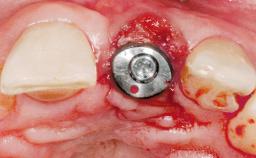

Late Placement of an Implant in a Maxillary Left Central Incisor Site

A 36-year-old female patient was referred for the replacement of the upper left central incisor (tooth 21), which had fractured. Although the tooth had been asymptomatic for many years, the crown began to loosen, at which time she presented to her dentist for an assessment. Teeth 21 and 22 had both been endodontically treated many years previously. She was a healthy individual and a non-smoker.